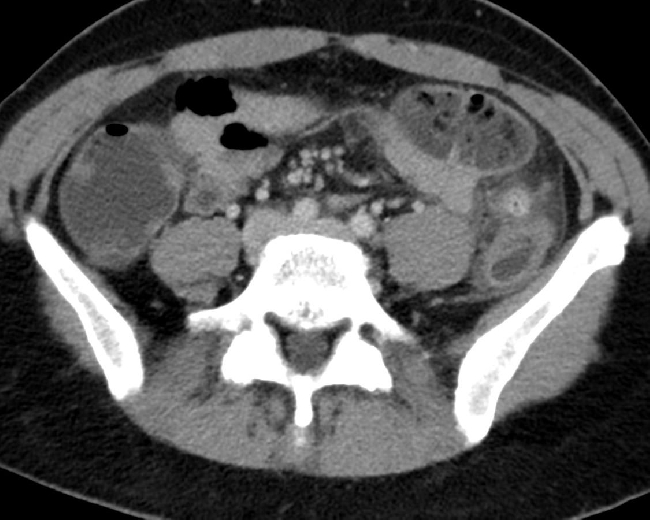

3. Welche der Aussagen zu dem axialen Bild trifft zu?

- a) Verdichtung mit umgebender Fettgewebsimbibierung ventral des Colon descendens

- b) Verdichtung mit umgebender Fettgewebsimbibierung ventral des Colon ascendens

- c) Verdichtung mit umgebender Fettgewebsimbibierung ventral des Colon transversum

- d) Verdichtung mit umgebender Fettgewebsimbibierung ventral der Gallenblase

- e) Kein suspekter Befund, reizlose Darstellung des Colons

5. Welche Diagnose stellen Sie?

- a) Emphysematöse Cholezystitis

- b) Perforierte Diverticulitis mit ausgedehntem Abszess

- c) Perforierte Diverticulitis mit ausgedehnter freier intraabdomineller Luft

- d) Einfache Diverticulitis ohne Perforation

- e) Gedeckt perforierte Diverticulitis